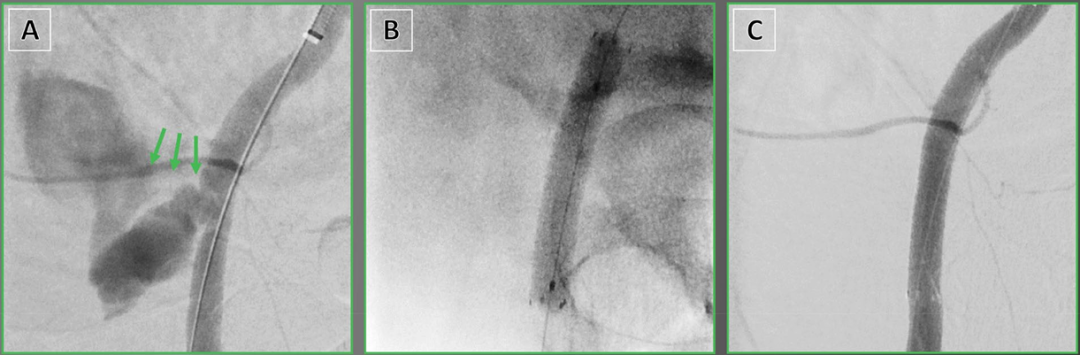

压裂治疗前后及球囊血管成形术后病变形态与IVUS评估的MLA代表性病例。A 初始血管造影显示右侧股总动脉存在重度钙化斑块。B 初始IVUS评估示术前最小管腔面积(MLA)为2.1 mm²(管腔直径:1.7 × 1.3 mm)。C、D 使用7.0 mm非顺应性球囊行球囊血管成形术后,后续血管造影及IVUS显示残余狭窄33%,术中MLA为5.8 mm²(管腔直径:3.0 × 1.7 mm)。E 压裂治疗后,最终血管造影显示满意影像,狭窄率17%。F 压裂后IVUS评估显示术后MLA为20.5 mm²(管腔直径:6.1 × 4.3 mm)。缩略语:IVUS,血管内超声;LD,管腔直径;MLA,最小管腔面积。

Viabahn覆膜支架用于造影剂外渗的腔内治疗。 一名79岁女性,经导管主动脉瓣置换术后发生股总动脉暴发性出血(绿色箭头)。B 经交叉操作后植入Viabahn覆膜支架。C 靶部位最终血管造影显示成功止血。

Viabahn覆膜支架用于血管破裂的腔内治疗。 一名52岁男性,因建筑工地工伤后出现腿部疼痛。A 血管造影显示腘动脉创伤性破裂(蓝色箭头)。B 植入Viabahn覆膜支架。C 靶部位最终血管造影显示血流恢复。

Viabahn覆膜支架用于输尿管-髂动脉瘘的腔内治疗。 一名80岁男性患者,既往病史复杂,包括结肠癌广泛手术治疗及化疗、多次尿路结石手术及输尿管支架植入,在拔除输尿管支架后出现大量血尿。A 随后的输尿管肾镜显示左侧输尿管与邻近的左侧髂内动脉之间存在瘘管连接(红色箭头),B 首先通过弹簧圈栓塞处理。C 因存在残留灌注(橙色箭头),D 植入Viabahn覆膜支架。E 输尿管造影显示瘘管无残留灌注。F 靶部位最终血管造影显示左侧髂动脉血流保留。